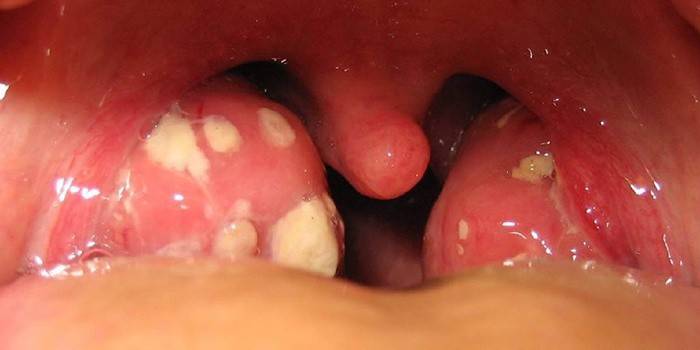

- amígdalas significativamente aumentadas;

- cavidades e abscessos na superfície das glândulas;

- inchaço dos arcos palatinos;

- friabilidade do tecido linfóide;

- vermelhidão das membranas mucosas;

- plugues nas amígdalas, formados a partir de tecido morto.